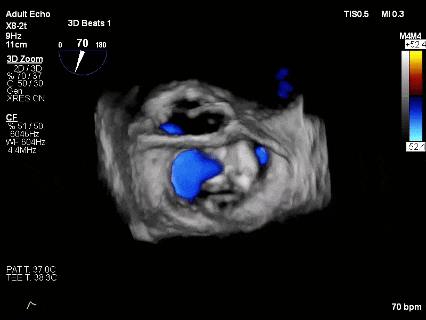

术前3D

术前3Dcolor

3D-TEE二尖瓣相关解剖学参数:后叶长度:22-25mm,前叶长度:31-34mm;瓣环AP径:47mm,ML径:48mm;瓣口面积:约7.8cm²;脱垂宽度:30mm,最大连枷间距:14mm。

3D-Zoom下观察组织桥稳定,内侧残余脱垂

最终结果3D-Zoom-color显示组织桥稳定,原脱垂区域前后叶对合部分的脱垂已消除,反流降至1+以下